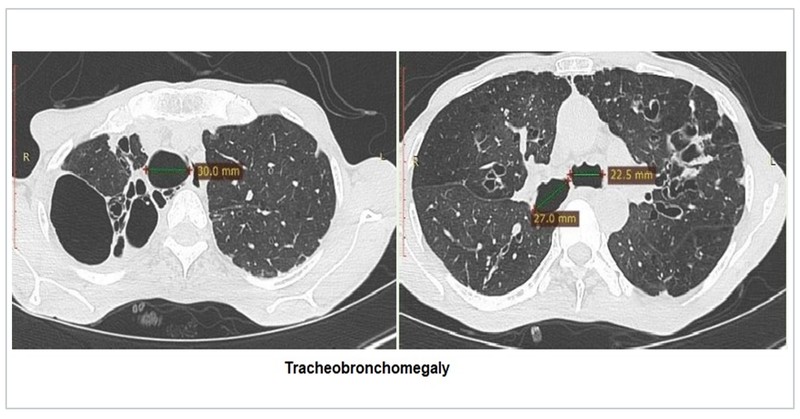

On the basis of CT types; bronchiectasis is classified as cystic, cylindrical and varicose. The signet ring sign, diagnostic of bronchiectasis is due to the dilated bronchus and accompanying pulmonary artery branch seen in cross-section resembling a signet ring. The bronchus and artery should be the same size normally. Tram-track sign denotes the thickened non-tapering (parallel) walls of cylindrical bronchiectasis. Syndromes associated with bronchiectasis may demonstrate tracheobronchomegaly (Mounier Kuhn) and tracheal diverticuli.